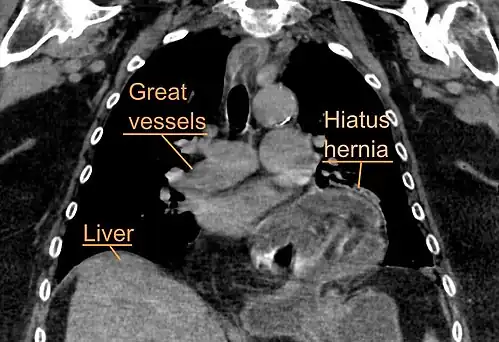

A hiatal hernia as seen on CT

A hiatal hernia as seen on CT -

A large hiatal hernia as seen on CT imaging

A large hiatal hernia as seen on CT imaging -

A large hiatal hernia as seen on CT imaging

A large hiatal hernia as seen on CT imaging -